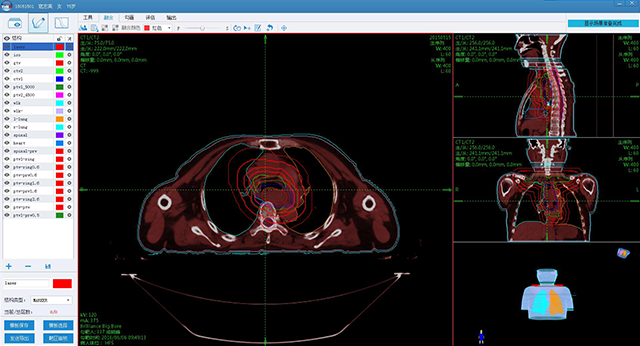

è‚؟çک¤و”¾ç–—ن؟،وپ¯هŒ–ن؛§ه“پ

ه®‰è¯؛ن؛‘و™؛è؟œç¨‹و”¾ç–—هچڈن½œه¹³هڈ°

è‚؟çک¤و™؛و…§هŒ»ç–—

ن؛§ه“پن¸ژو•ˆهٹ³